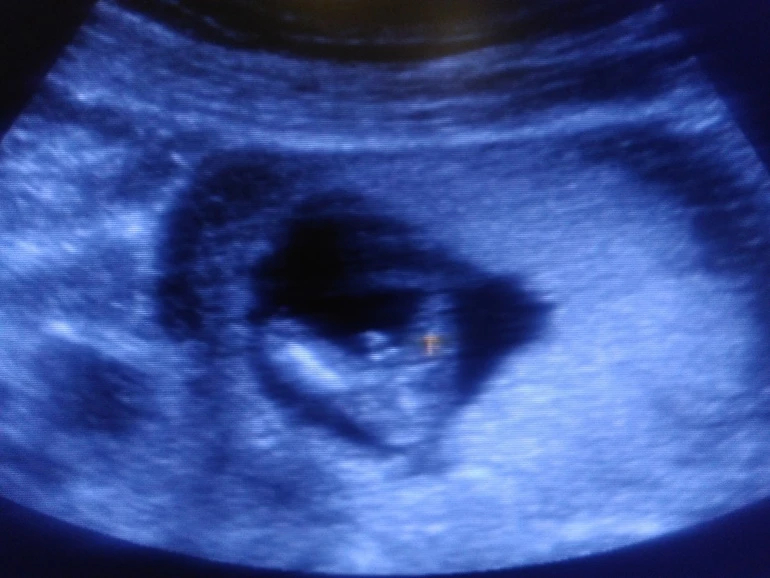

Ну вот и позади первый скрининг 12+3, познакомился папа с пузожителем, все хорошо и закрашиваю значок- у нас мальчик!!! Ах, как папа счастлив, и слышать не хотел, что может быть девочка. По ходу сын услышал его мольбы и отрастил в первую очередь "началко", а теперь будет равномерно от "началка" расти))))))))) Почему началко?!- это муж мой так говорит, мол это у него не конец, а началко, он от него вверх и вниз равномерный)))))))))))))) Активный такой мальчуган, еле рассмотрели все! Сказала врач, что редко такое бывает в 12 недель, но "причандал" серьезный, сказала, что сомнений нет-пацан, и показала со всех сторон папину радость))) лежит на спине, пинается ногами и сосёт палец. Я конечно не знаю, что бы там не говорили за кишечник, но я со вчерашнего дня слышу возню именно в одном месте, уровень широкой резинки леггинсов, именно очень похоже на шевелюшки. Ну вот так и получилось, как я предполагала с самых первых дней, - будет мальчик - это они такие капризные))) не успела // увидеть, а уже кипишу сколько пережила, что в 7 недель казалось, что я уже недель 20 беременная, нервотреп казявоШный ))))))). Но все самое интересное ещё только впереди. А вот и папина гордость

Папина мечта: